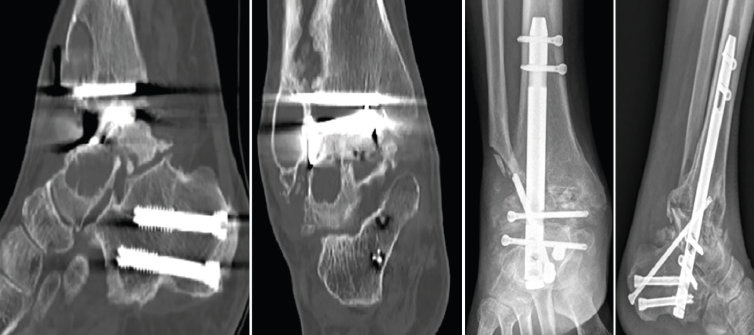

Figura 3. Imágenes del clavo tibiotalocalcáneo roto a través de la trinchera ósea y maniobra de extracción con guías endomedulares ayudadas por la impactación directa en la muesca realizada en el clavo.

Se reintervino al paciente realizando la extracción del fragmento distal del clavo con el sistema extractor del mismo. Para la extracción del extremo proximal fue necesario, además de la utilización de las guías curvadas, abordar el foco de la pseudoartrosis hasta visualizar el clavo y, con una fresa de alta velocidad, hacer una muesca en el mismo. Mediante la percusión sobre un escoplo apoyado en la muesca realizada en el clavo y con la ayuda de las agujas guía introducidas a través del clavo, se consiguió la extracción del extremo proximal a través de la planta del pie (Figura 3). Se legró la superficie articular tibiotalar y se colocó injerto de cresta ilíaca, fijando la artrodesis con una placa TTC (Palex Medical), aunque la articulación subtalar estuviese artrodesada, para dar mayor solidez al montaje.

Figura 4. Imágenes de tomografía computarizada con lisis alrededor de la prótesis con deformidad en varo. Se aprecia la osteosíntesis para la osteotomía del calcáneo realizada previamente. Imágenes radiográficas tras la artrodesis tibiotalocalcánea con clavo retrogrado con tornillo tibiotalocalcáneo del calcáneo a la tibia oblicuo.

Se realizó, por vía transperoneal, la extracción de la prótesis de tobillo y una ATTC con clavo Phoenix® (Zimmer Biomet) de 11 mm de diámetro y 180 mm de longitud, reforzando el montaje con un tornillo oblicuo desde el calcáneo a la tibia, como en el caso número 2. El peroné extraído por el abordaje lateral se utilizó como injerto autólogo corticoesponjoso (Figura 4).